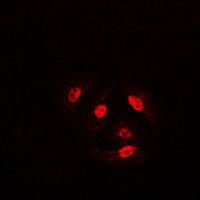

Immunofluorescent analysis of Cofilin (Phospho-S3) staining in HeLa cells. Formalin-fixed cells were permeabilized with 0.1% Triton X-100 in TBS for 5-10 minutes and blocked with 3% BSA-PBS for 30 minutes at room temperature. Cells were probed with the primary antibody in 3% BSA-PBS and incubated overnight at 4 °C in a humidified chamber. Cells were washed with PBST and incubated with a DyLight 594-conjugated secondary antibody (red) in PBS at room temperature in the dark.